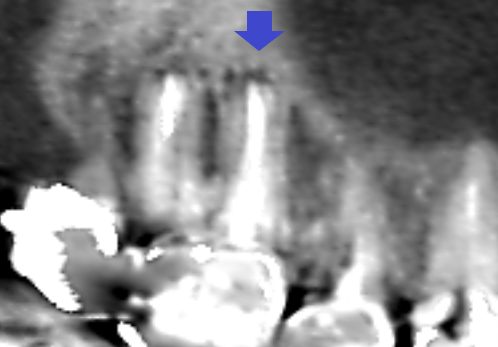

精密根管治療6カ月後の経過観察時の冠状断のCT画像です。近心頬側根の先にあった膿の影が消失し歯槽骨が再生してきています。